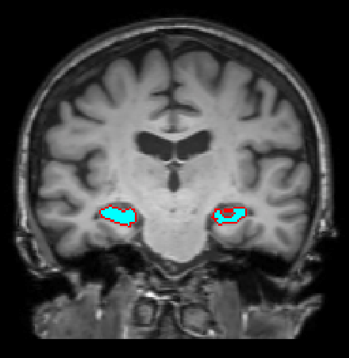

Subcortical segmentation of the fetal brain in 3D ultrasound using deep learning

NeuroImage

·

01 Jul 2022

·

doi:10.1016/j.neuroimage.2022.119117